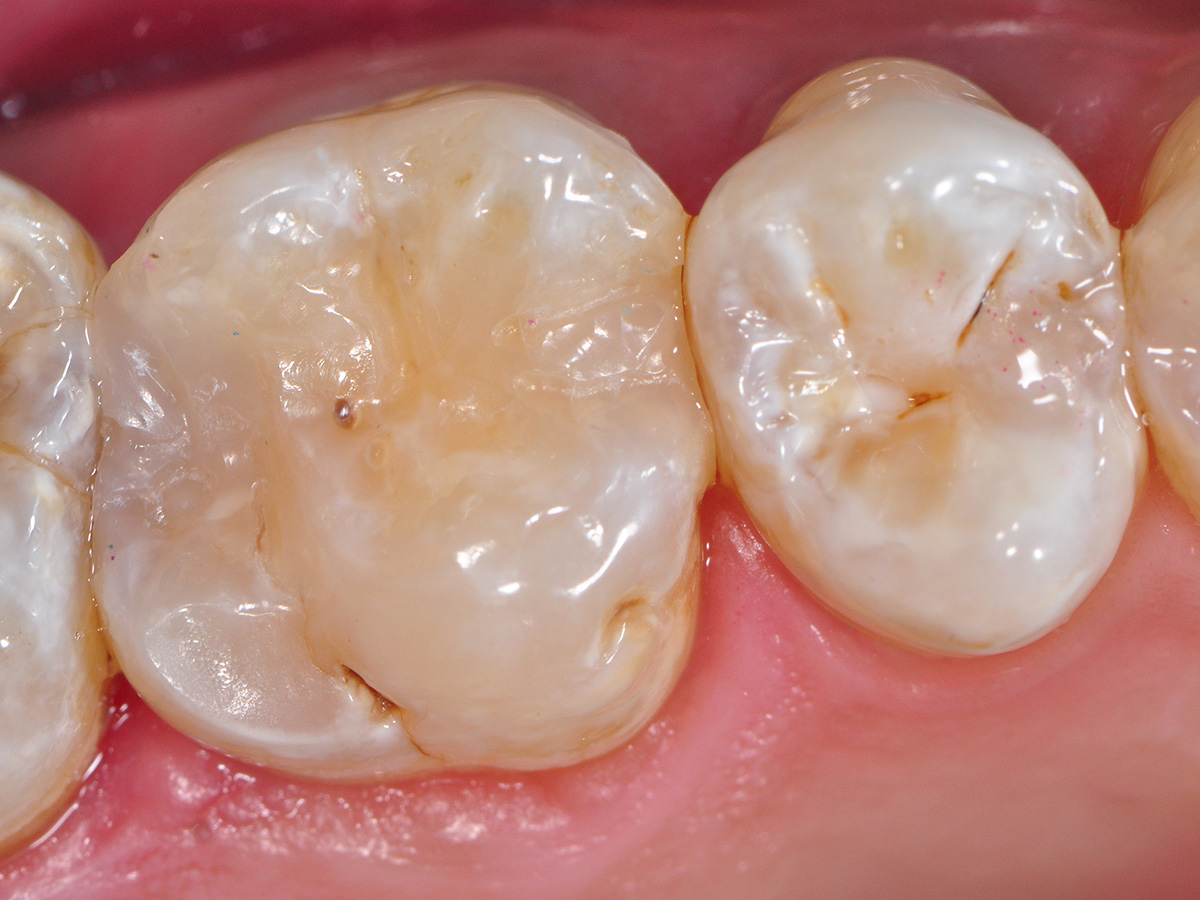

Abbildung 1

Die Ausgangssituation zeigt einen durch Bruxismus abradierten und auch leicht erodierten Zahn 16 mit einer Approximalkaries mesial und distal unter der ausgewaschenen Füllung.